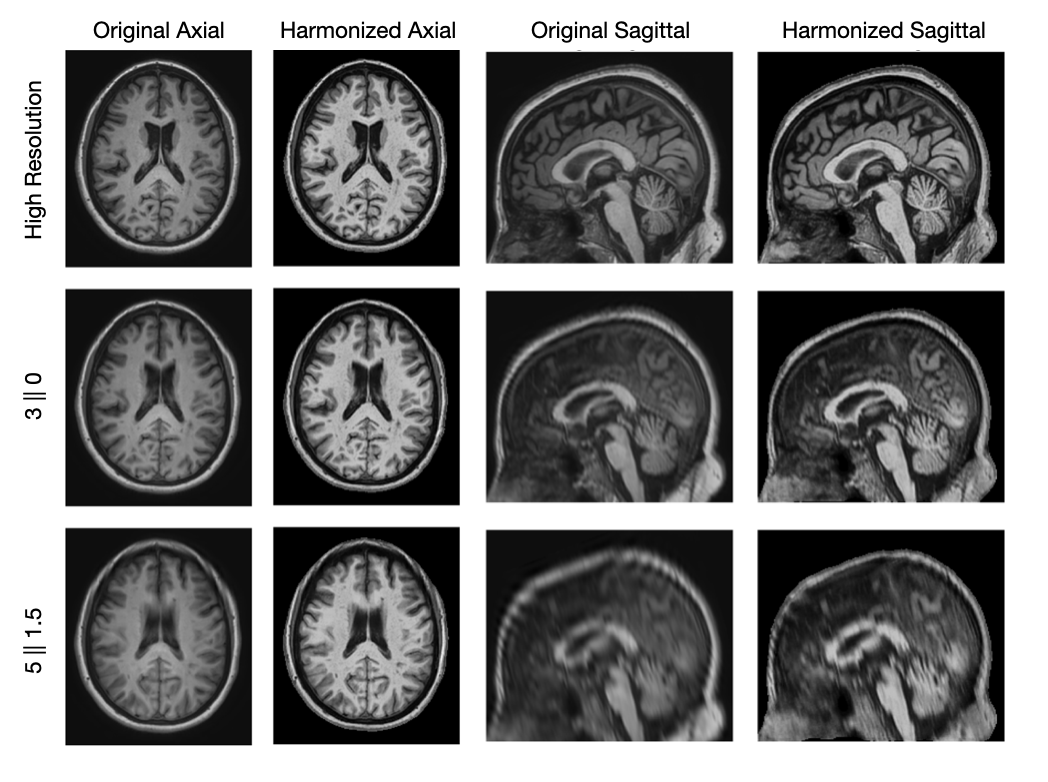

Figure 2 shows the original and harmonized registered T1w images at HR and two simulated LRs demonstrating the impact of resolution degradation. We show a LR image simulating an axial acquisition at a resolution of 30conditional303\|0, which is the best 2D resolution we investigate and a LR image simulating a sagittal acquisition at a resolution of 51.5conditional51.55\|1.5, which is the worst resolution we investigate. As the resolution gets worse, we observe that the image appears more blurry due to the slice thickness. The T2w and T2w-FLAIR images behave similarly to the T1w images.

Refer to caption

Figure 2: The original and harmonized registered T1w images at HR and two LRs, all images are shown with the same look-up table.